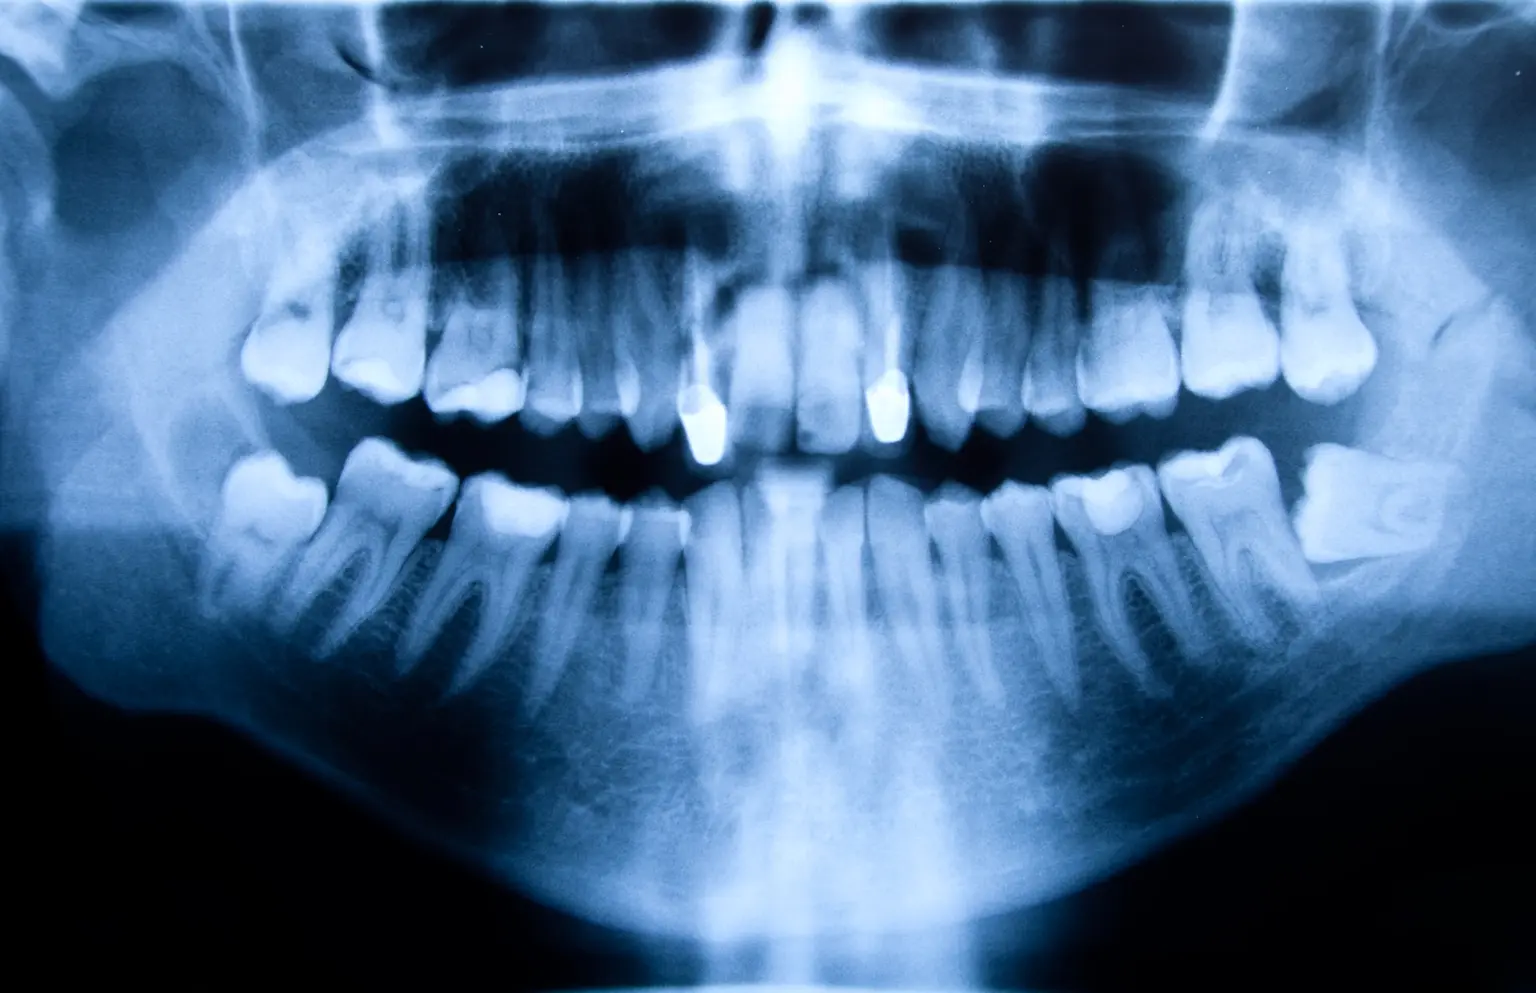

Un cabinet dentaire regroupe des professionnels de santé spécialisés dans les soins bucco-dentaires. Il s'agit d'un espace dédié à la prévention, au diagnostic et au traitement des pathologies dentaires.

L’équipement du cabinet dentaire doit répondre à des exigences strictes en matière de qualité et d’hygiène. Parmi les équipements de base, on retrouve :

Fauteuil dentaire

Matériel de radiographie

Autoclave pour la stérilisation

Instruments dentaires et fournitures d’hygiène (gants, masques…)